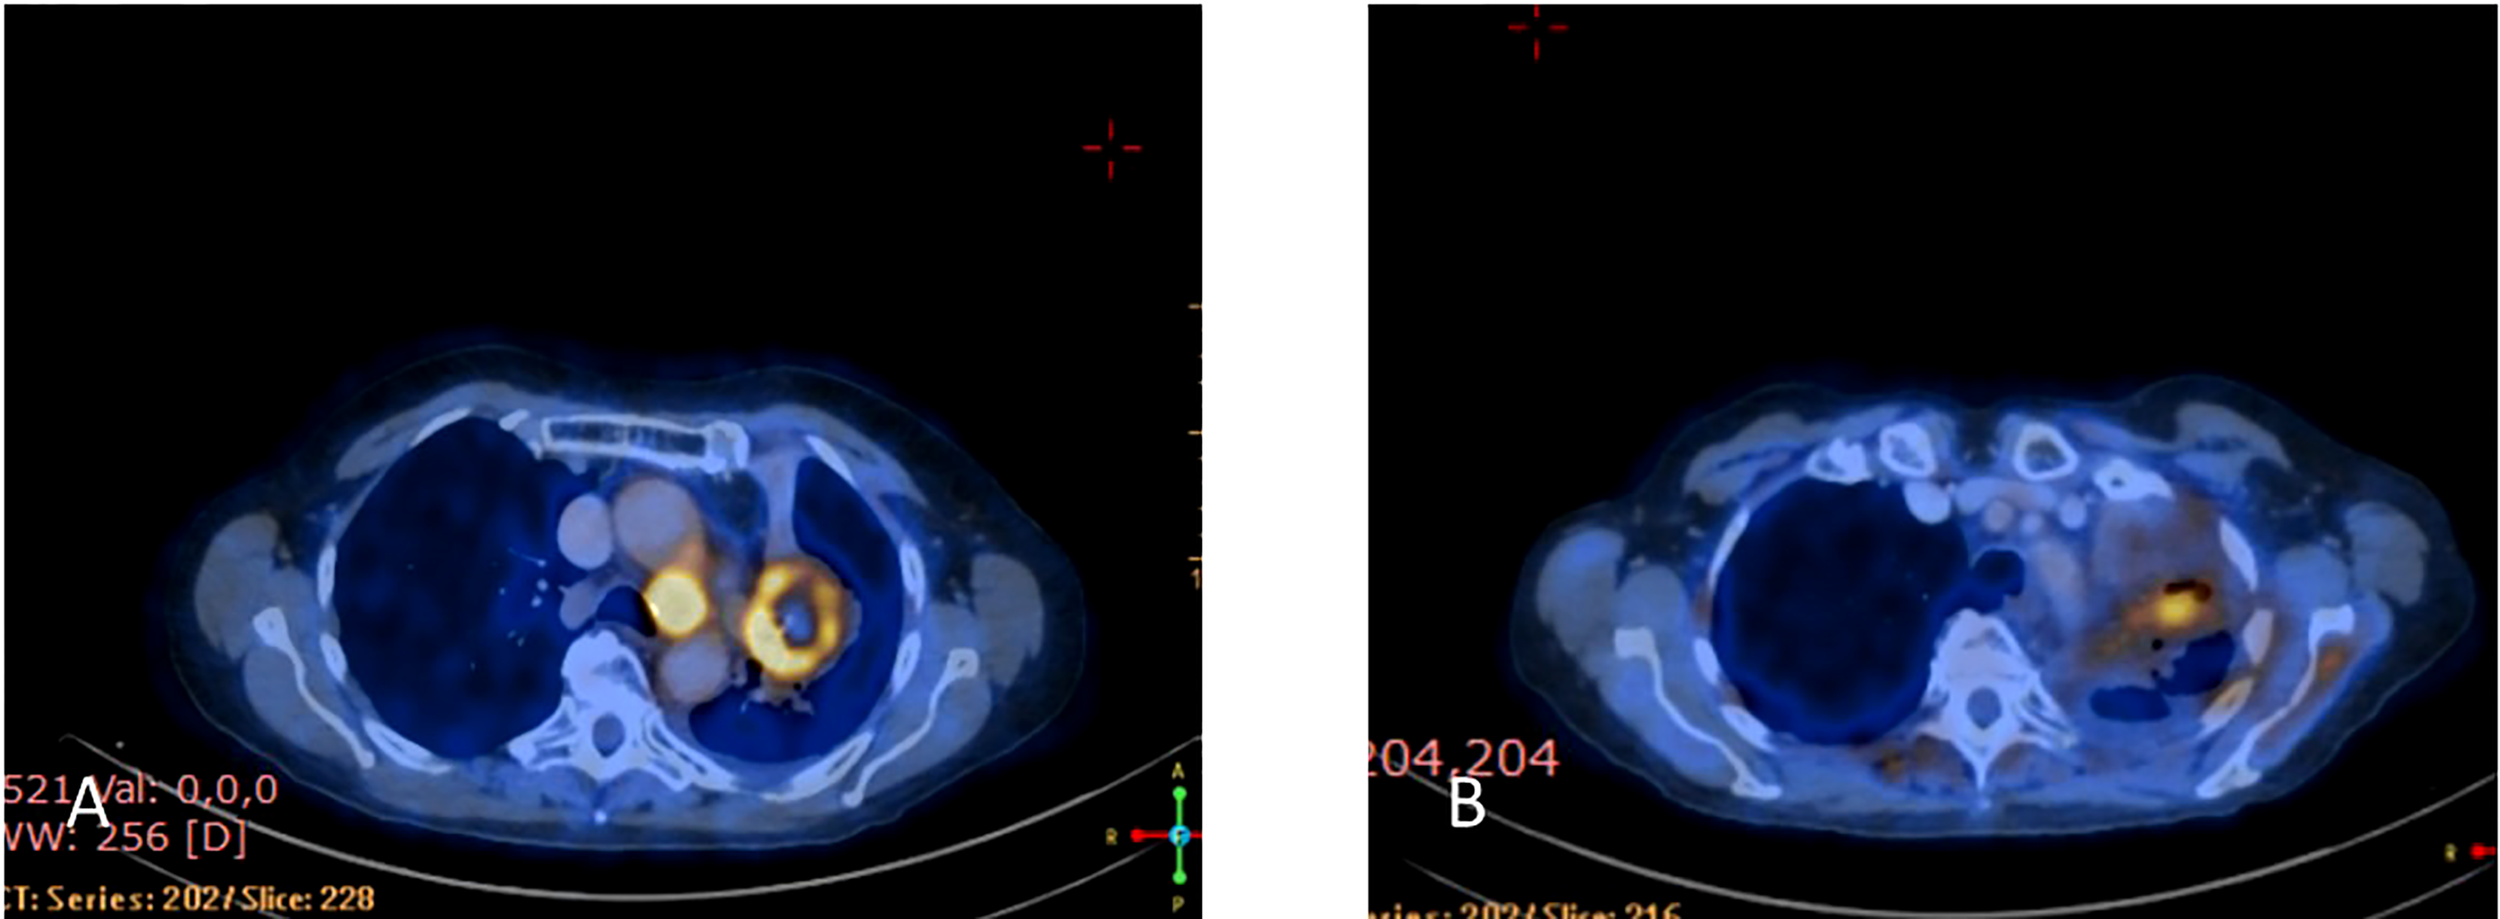

Upon disease progression in October of 2021, cfDNA liquid biopsy demonstrated EGFR L858R of 2.3%; V83L of 2.8%; with MET amplification. Brain MRI showed no metastases. Treatment with osimertinib (80mg daily) was continued. The decision was made to add 1050 mg of Amivantanab every two weeks to the patient’s treatment at this time. After four rounds of treatment, resulted in clinical and RECIST partial response (Figures 7A, B).

Figure 7

(A) Coronal PET-CT scan from October 2021 shows a left lung mass and ipsilateral pleural effusion with increased uptake of FDG-18, indicating disease progression on Osimertinib. (B) Three months later, January 2022, showed significantly decreased uptake of FDG-18, indicating partial response following adding Amivantamb to Osimertinib.

In March 2022, treatment was continued, with Amivantanab reduced from two-week intervals to three-week intervals due to grade 2 adverse events (diarrhea and paronychia). Liquid biopsy in May 2022 demonstrated total eradication of MET and EGFR from the cfDNA in the blood (Figure 8). Eight months later, the patient is still responding to the combination therapy.

Figure 8

Guardant360 response map for circulating free tumor DNA following each treatment line.